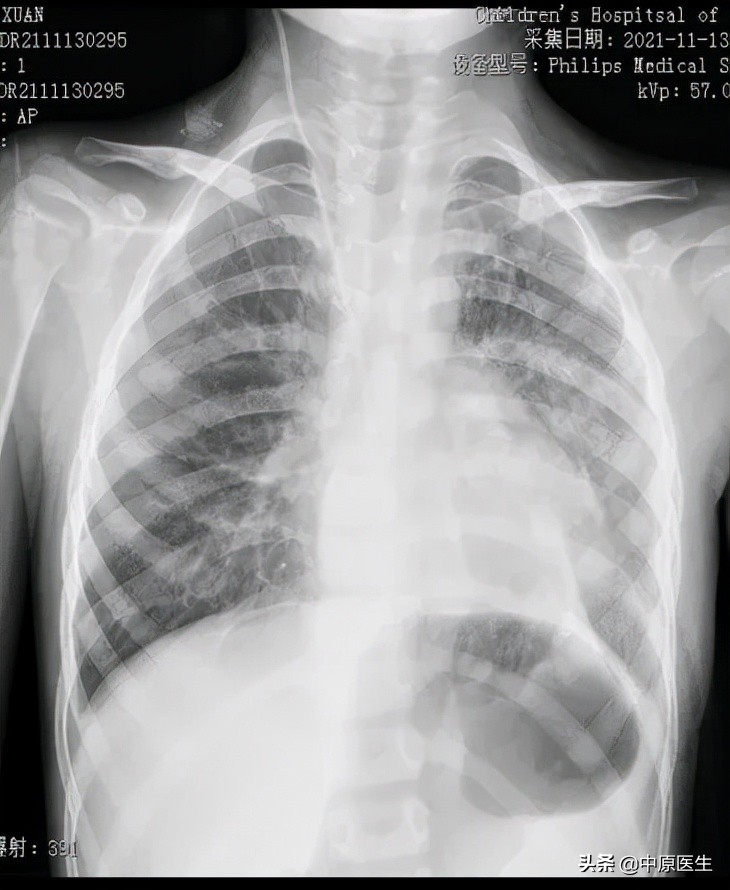

在河南省儿童医院胸心外科,程文哲医师诊断楠楠为先天性膈疝。影像资料显示,楠楠的左肺严重受压,如果继续压迫,左肺将失去功能甚至危及生命。

术后在胸腔镜视野下,可看到楠楠的左侧胸腔内充满了胃和肠子,而左肺则受压变小,医生们帮助腹腔各脏器回到它们原本的位置,紧接着修补了缺损的膈肌,最后让受压的左肺重新膨开了。

胸腔镜手术的顺利完成大大减少了对患儿创伤,为预后打下了良好的基础。